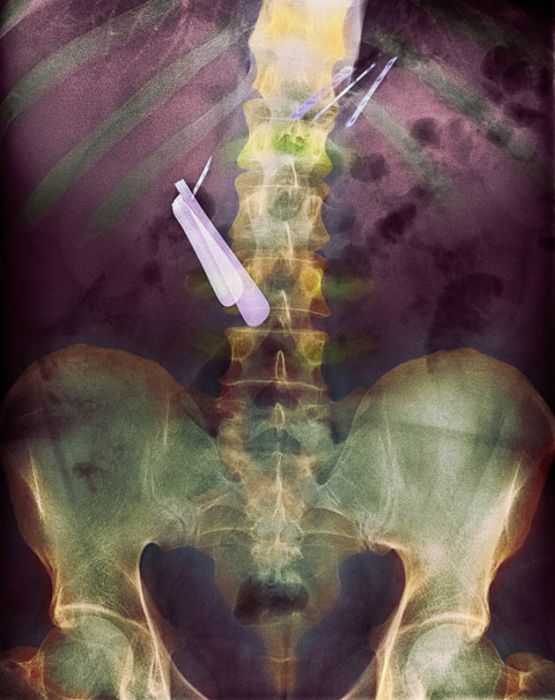

Жуткие рентгеновские снимки

Порой даже не верится, с какими странными и необычными повреждениями в травматологию могут поступить пострадавшие. Всю эпичность профессии врачей травматологии могут с легкостью подтвердить рентгеновские снимки. Просто жесть, да и только..